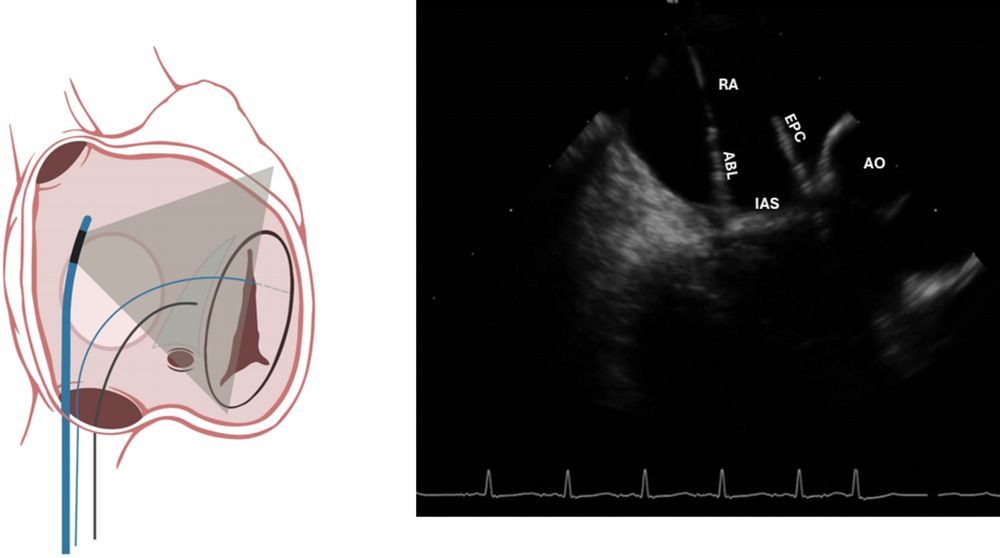

🫀 Fresh: Zero-fluoroscopy EP catheter navigation guide via ICE—literature review at #IJCVI!

🌐

A practical guide and review of the literature on zero-fluoroscopy electrophysiology catheter navigation by intracardiac echocardiography

The International Journal of Cardiovascular Imaging - Navigation of electrophysiology (EP) catheters using intracardiac echocardiography (ICE) is an emerging technique to avoid fluoroscopy and...

doi.org